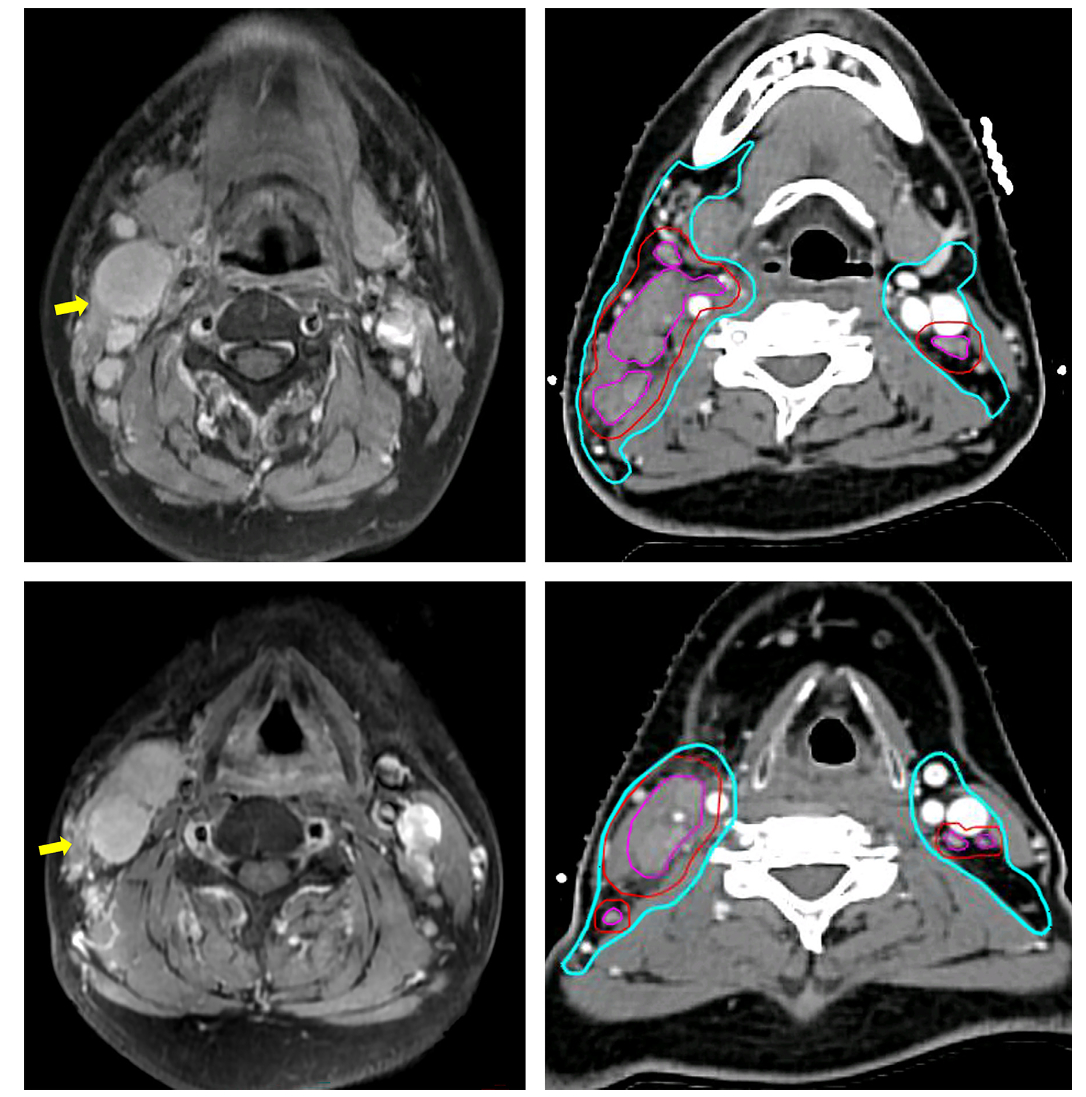

在淋巴结临床靶区的勾画方面,高危淋巴结靶区至70戈瑞等效剂量的外放边界对于无淋巴结外侵犯的患者建议为零至五毫米的灵活范围,而对于伴有晚期淋巴结外侵犯的患者则强烈推荐五至十毫米的外放边界。对于可疑但未明确的淋巴结,新版指南建议不添加外放边界并将处方剂量设定为60戈瑞等效剂量。低危淋巴结靶区至50戈瑞等效剂量的勾画推荐涵盖高危靶区并覆盖相应的淋巴结区域,处方剂量为50戈瑞等效剂量。在选择性淋巴结区域的覆盖上,双侧咽后淋巴结和II区淋巴结仍建议常规覆盖至50戈瑞等效剂量,III区和Va区也推荐双侧覆盖,而IV区和Vb至Vc区则仅在同侧III区或Va区受累时才需覆盖。Ib区的覆盖指征包括Ib区淋巴结受累、颌下腺受累以及引流至Ib区的首发部位受累如下口腔或鼻腔前半部,但颌下腺在未受累时可以考虑豁免照射。在淋巴结靶区的解剖边界方面,II区的头侧边界应延伸至颅底,尾侧边界的设定则根据受累水平的不同而有所区别,对于I、II、III和Va区受累者延伸至受累水平下一级,对于IV或Vb至Vc区受累者则延伸至锁骨头上方并确保在受累淋巴结下方两厘米边界,同时IV区前界从胸锁乳突肌前缘修改为舌骨下带状肌后缘,这有助于减少对甲状腺的不必要照射。

图2 淋巴结临床靶区的勾画